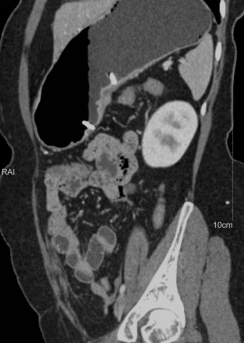

胃癌患者术前进行专科化、规范化的CT扫描;进行结构化诊断报告书写,术前影像学分期报告。

规范胃癌患者的CT扫描技术方案、诊断报告书写模式,提高胃癌术前分期诊断准确率,为临床制定治疗方案提供充分依据,与其他检查方法互补,实现个体化、精准医疗。